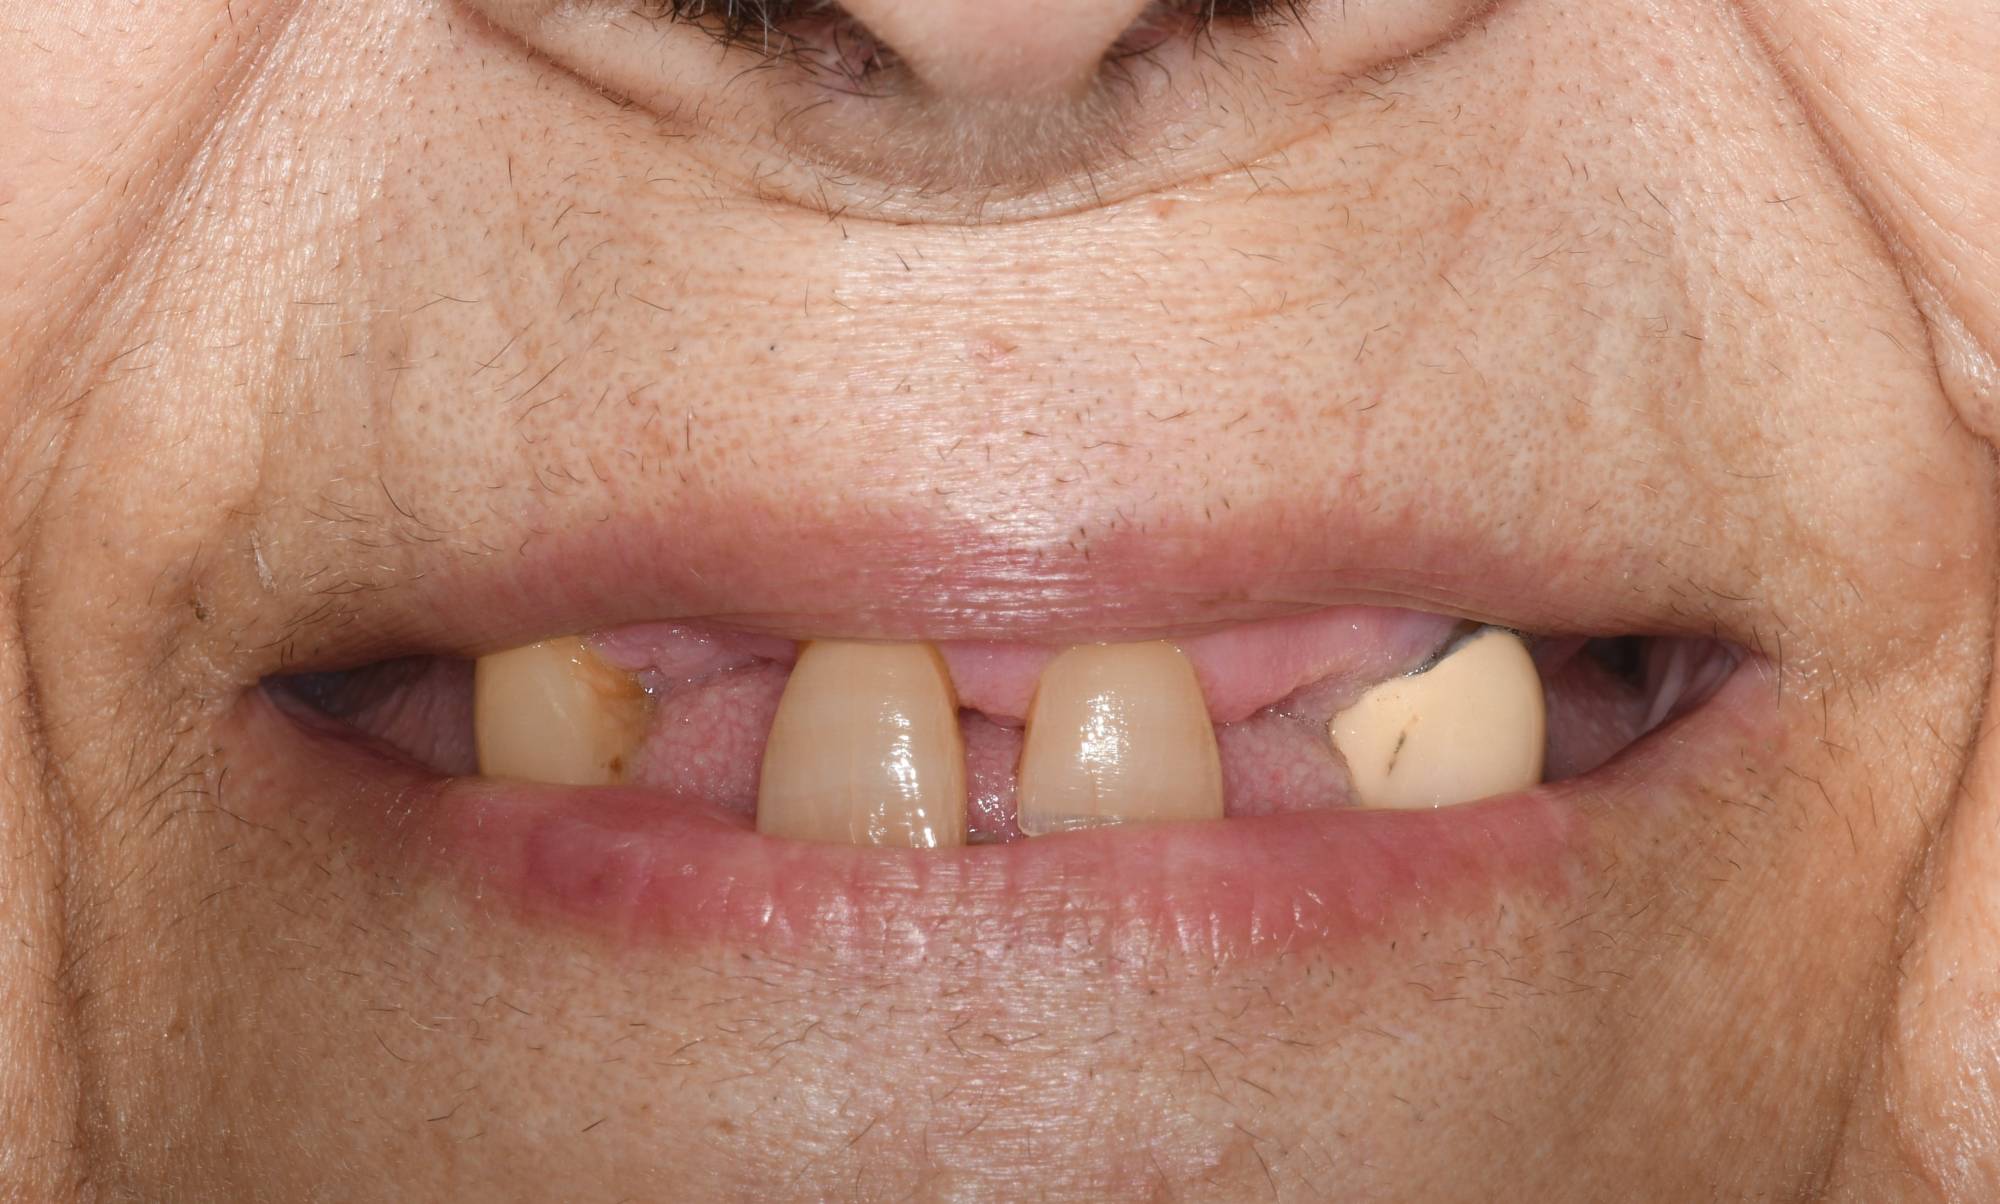

Riesci ad immaginare come sia difficile masticare quando ti rimangono solo pochi denti? La signora che si era presentata nel mio Studio era esattamente nelle condizioni che vedi nella prima foto. Oltre al lato estetico, ad essere compromessa era la funzione masticatoria. La signora aveva solo quattro denti frontali che si muovevano, e nessun altro elemento posteriore. Persino mangiare le risultava difficile.

Normalmente il destino della paziente sarebbe quello di passare da quella situazione alla classica dentiera. Il suo desiderio era però di avere i denti fissi.